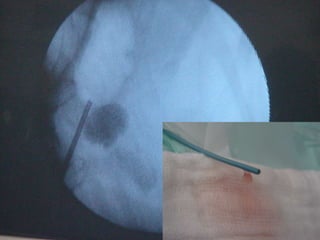

O documento discute o tratamento de urolitíase, especificamente a remoção de cálculos renais através de nefrolitotripsia. A cirurgia aberta é agora muito restrita devido aos avanços da ESWL e procedimentos endourológicos menos invasivos como ureteroscopia e cirurgia percutânea. A cirurgia laparoscópica está substituindo a cirurgia aberta como técnica menos invasiva que combina a tecnologia endourológica com a laparoscópica preservando